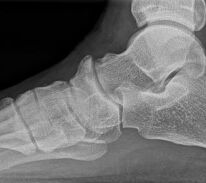

Abbildung 1: Plantarer und dorsaler Sporn im Röntgenbild und im MRT

Abb. 1a und Abb. 1b: großer dorsaler Fersensporn und ein minimaler plantarer Sporn, Patient, 50 Jahre.

Abb. 1c: Bild eines isolierten großen plantaren Fersensporns. Patientin, 32 Jahre.

Zum Lesen der Bildbeschreibung und zur Vollansicht bitte die Bilder anklicken. Bilder: Manfred Thomas.

Dorsaler Fersensporn: Dorsale Fersenschmerzen können auch durch einen echten dorsalen Fersensporn entstehen (siehe Abb. 1). Dieser entsteht als knöcherne Ausziehung durch Verkalkung der Achillessehne an ihrem Ansatz.